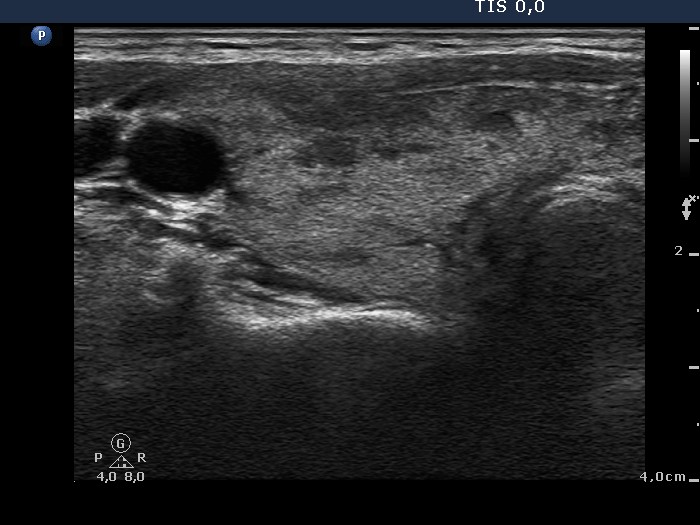

Follow-up investigation 33 months after first visit (ultrasonographic picture 1)

Patient on daily 20 mg methimazole therapy in euthyroid state

Right lobe, transverse scan. The proportion of hypoechoic areas has significantly decreased.